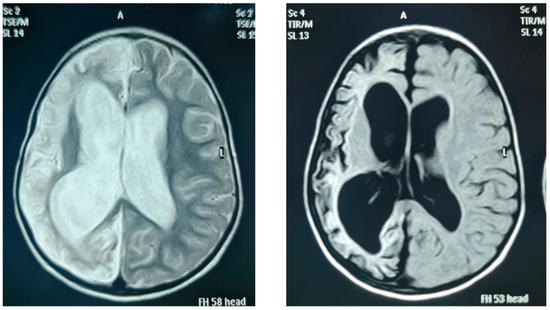

| FIII/14 | Large left cerebral infarction with normal pituitary gland |

| FIV/21 | Unilateral cerebral diffuse cortical gliosis, atrophy with evacuee dilatation of the ipsilateral ventricle, prominent sulci, and hypoplastic anterior pituitary gland |

| FIV/22 | Right cerebral hemiatrophy, with marked loss of white, subcortical, and deep matter volumes with prominent sulci, and secondary ballooning of the right lateral ventricle with no midline shifting, right temporal cystic encephalomalacia |